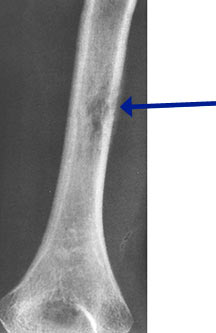

- May arise from any bone and any site within a bone (epiphyseal, metaphyseal, diaphyseal)

- Radiographically variable appearance: may appear benign (geographic) or malignant (permeative or moth eaten)

Radiographic Presentation